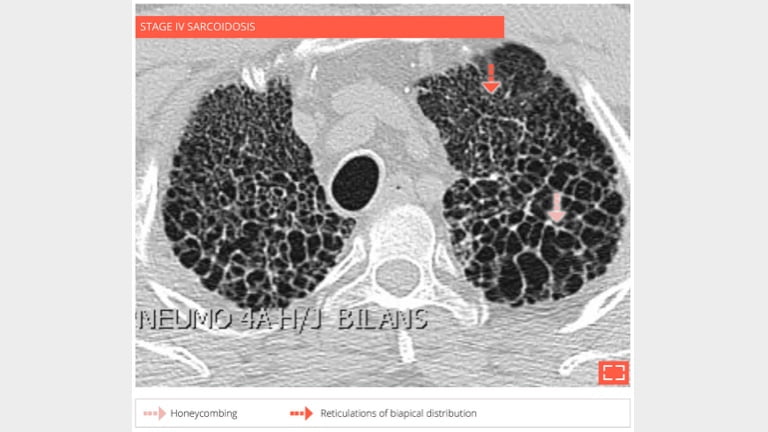

4. Honeycombing

honey-4

56-year-old man with history of sarcoidosis. Typical honeycombing in a upper lobe distribution.

5. Honeycombing

honey-5

• Coronal reformation in the same patient shows the association of honeycombing and reticulation in lung apices.

• Distribution of fibrosis to apices makes this fibrosis incompatible with UIP.